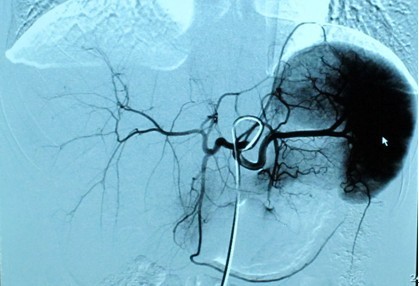

血管内介入是指:使用1-2mm 粗的穿刺针,通过穿刺人体表浅动静脉,进入人体血管系统,医生凭借已掌握的血管解剖知识,在血管造影机的引导下,将导管送到病灶所在的位置,通过导管注射造影剂,显示病灶血管情况,在血管内对病灶进行治疗的方法。包括:动脉栓塞术、血管成形术等。常用的体表穿刺点有股动静脉、桡动脉、锁骨下动静脉、颈动静脉等。

(1)肿瘤的栓塞:肝癌、肺癌、盆腔等部位肿瘤均可通过导管将栓塞剂注入供血动脉,阻断其血运,达到“饿死肿瘤”的目的。

(2)出血的栓塞:晚期肿瘤常引发大出血,如不及时控制,常引起其它并发症,导致死亡。如肺癌、膀胱癌、胃底食管静脉曲张破裂等,该类患者应行急诊介入治疗,栓塞其供血血管,控制出血。如支气管动脉、髂内动脉、胃冠状静脉等。